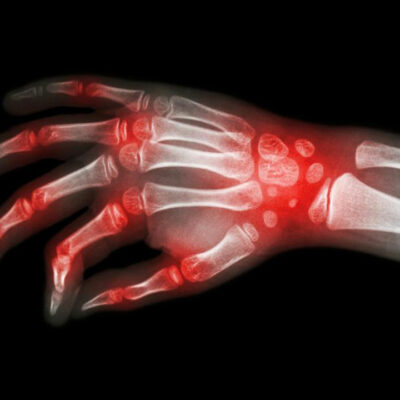

Lupus and rheumatoid arthritis are both autoimmune conditions that are often confused to be the same. The fact that these – rheumatoid arthritis, lupus are autoimmune diseases makes their symptoms similar too. Auto immune diseases are typically those conditions where the immune system of the body attacks healthy cells, causing inflammation, swelling, and pain in the affected areas.